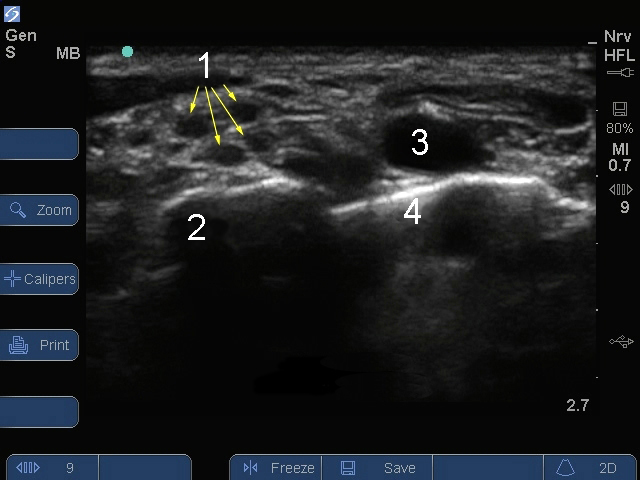

Bild: S Series, Plexus brachialis, supraklavikulare Ebene 1

Nerve (Nerv)

Erste Rippe

Arterie

Lunge